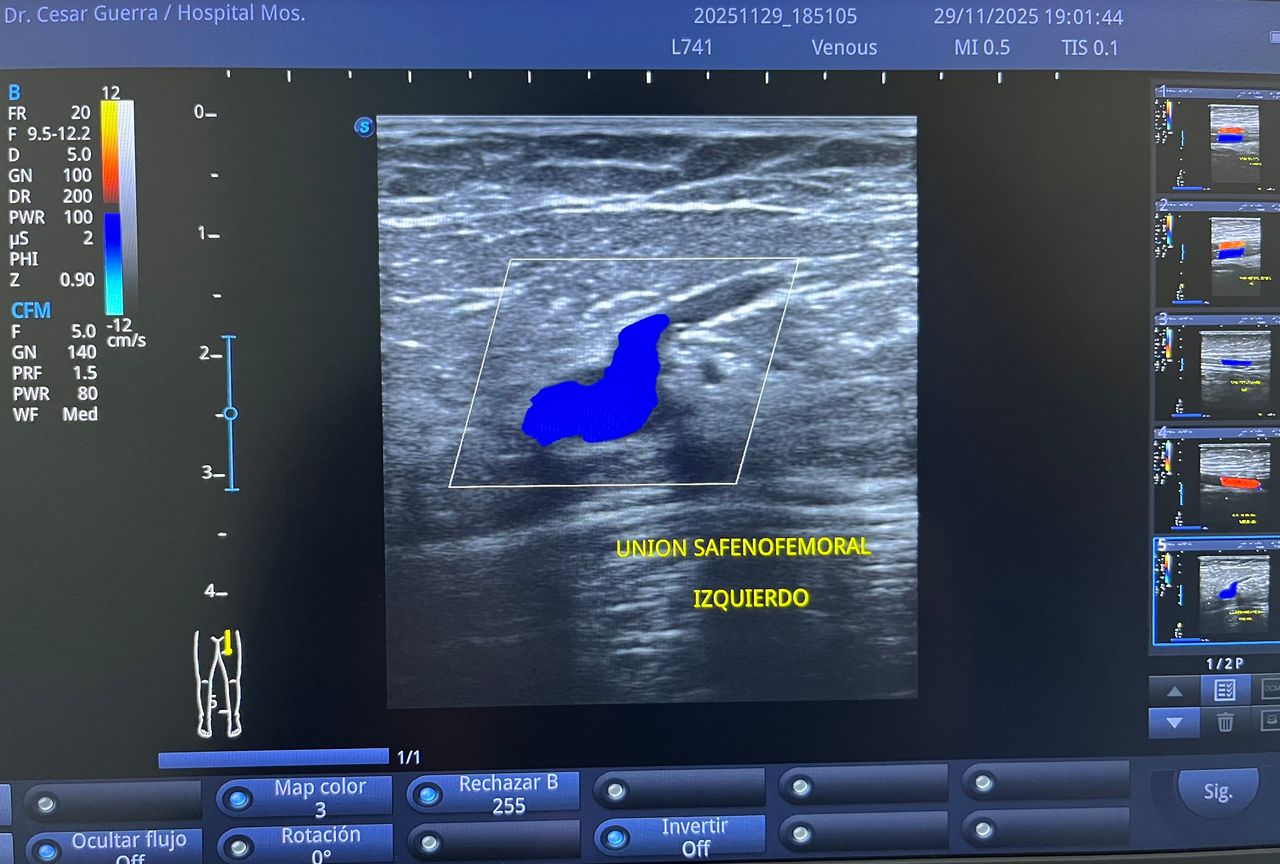

Médico general con 15 años de experiencia, master en enfermedades infecciosas y antibioticoterapia por parte de la Universidad Cardenal Herrera en Valencia, ademas de diversos diplomados en el área de Infectología y Parasitología, Urgencias, Imagenología y Medicina del Trabajo. He laborado en Hospitales y Clínicas en el área de Urgencias, en Laboratorios realizando estudios de Imagen, en especifico ultrasonidos de todo tipo desde básicos hasta avanzados incluidos los obstétricos estructurales, en Secretaría de Salud del Estado de Querétaro realizando ultrasonidos obstétricos para la detección de malformaciones en los tres trimestres del embarazo en diversos centros de salud, como médico de Empresas en el campo de Salud Laboral y actualmente en este consultorio en donde para su mejor atención y siempre buscando integrar la mayoría de las herramientas diagnosticas cuento con equipo de ultrasonido como apoyo en la exploración del paciente o como servicio diagnostico por imagen, realizo ultrasonidos convencionales (hepatobiliar (hígado, páncreas, vesícula y bazo), vías urinarias, ginecológico abdominal y transvaginal, tiroideo, prostático, testicular, pared abdominal) y especializados (dopler obstétrico en los 3 trimestres de embarazo), musculoesquelético en lesiones deportivas. También cuento con un equipo de electrocardiograma de 12 derivaciones para monitoreo completo del funcionamiento cardiaco, espirometria para evaluar la función pulmonar en la consulta, pruebas rápidas que se realizan en consultorio para detectar de forma mas precisa enfermedades infecciosas como Influenza A y B, covid19, infecciones urinarias, dengue, zika, chikungunya. Cuento con diversas vacunas para prevención de enfermedades. Siempre con el objetivo de dar el mejor servicio y atención a su salud. Lo espero en consulta para escucharlo y estudiar su caso de la forma más completa posible, estoy seguro de que tendremos las mejores opciones para su tratamiento. Mi tranquilidad es que usted se vaya con todas sus preguntas e inquietudes resueltas.